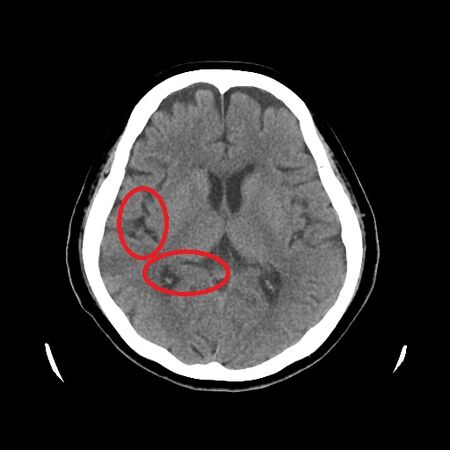

▲精神科醫師經由影像檢查及認知功能評估,診斷患者罹患輕度失智症併發精神行為症狀。(圖/亞大醫院提供)

以該名個案的情況來說,已經導致家中爭吵不斷,一度要發生肢體衝突,讓家庭氣氛緊繃到極致,家人們十分困惑與挫折,不得不求助就醫。吳佳錚表示,經透過認知功能量表篩檢後,察覺患者短期記憶已有明顯退化跡象,進一步安排抽血與腦部核磁共振影像檢查,也發現他的大腦顯著萎縮,最終確診為輕度失智症合併憂鬱與妄想等精神行為症狀。

▲腦部核磁共振影像檢查出大腦顯著萎縮。(圖/亞大醫院提供)